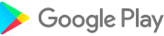

AnSo 是一种方便的资源,旨在帮助麻醉师在繁忙的手术室内以高效的方式识别常见的声解剖学。它是由对超声和局部麻醉教学感兴趣的执业麻醉师创建的。

AnSo 不仅有助于识别目标结构,还有助于识别所有周围的声解剖学。对声解剖学更全面的了解有助于检测解剖变异性,提高手术的安全性和有效性,并促进学习和教学。

- 超过 250 个超声图像,具有超过 1500 个声解剖学颜色叠加,

AnSo 是一种方便的资源,旨在帮助麻醉师在繁忙的手术室内以高效的方式识别常见的声解剖学。它是由对超声和局部麻醉教学感兴趣的执业麻醉师创建的。

AnSo 不仅有助于识别目标结构,还有助于识别所有周围的声解剖学。对声解剖学更全面的了解有助于检测解剖变异性,提高手术的安全性和有效性,并促进学习和教学。

- 超过 250 个超声图像,具有超过 1500 个声解剖学颜色叠加,